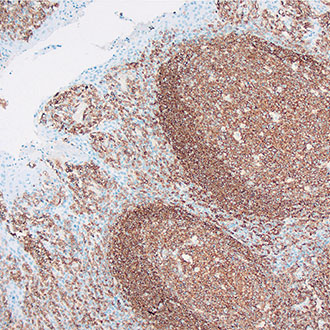

CD45

CD45 -